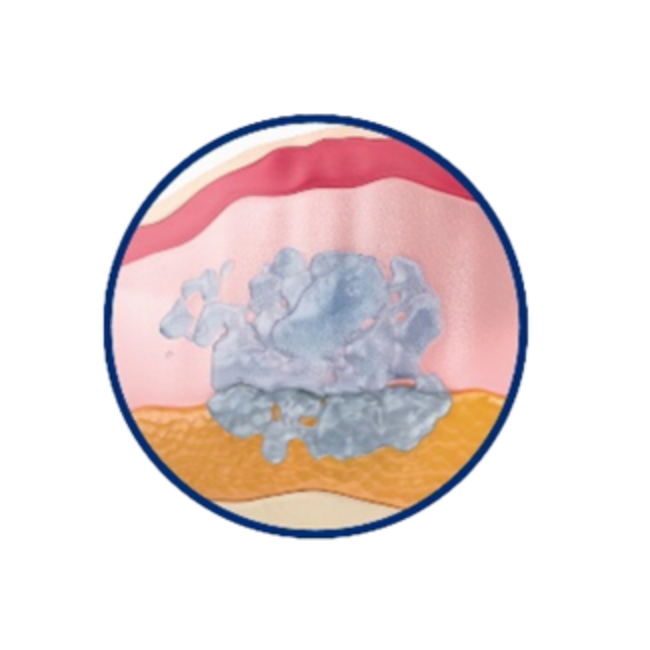

組織相容性佳 宛若天生膚感

實際切片圖

組織相容示意圖

OBT女神[動態]玻尿酸TM的微導親膚科技,讓玻尿酸膠體的質地柔韌,與肌膚緊密貼合,彷若天生膚感;同時具備良好的支撐度,強化臉部輪廓亮彩。通過美國FDA、歐盟CE與台灣衛福部核可上市,超過2,500位研究個案及全球上市後長期追蹤研究,擁有美麗同時安心。